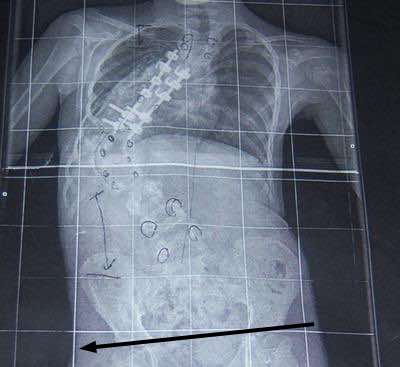

This is a bad scoliosis; unlikely yours is anything like this.